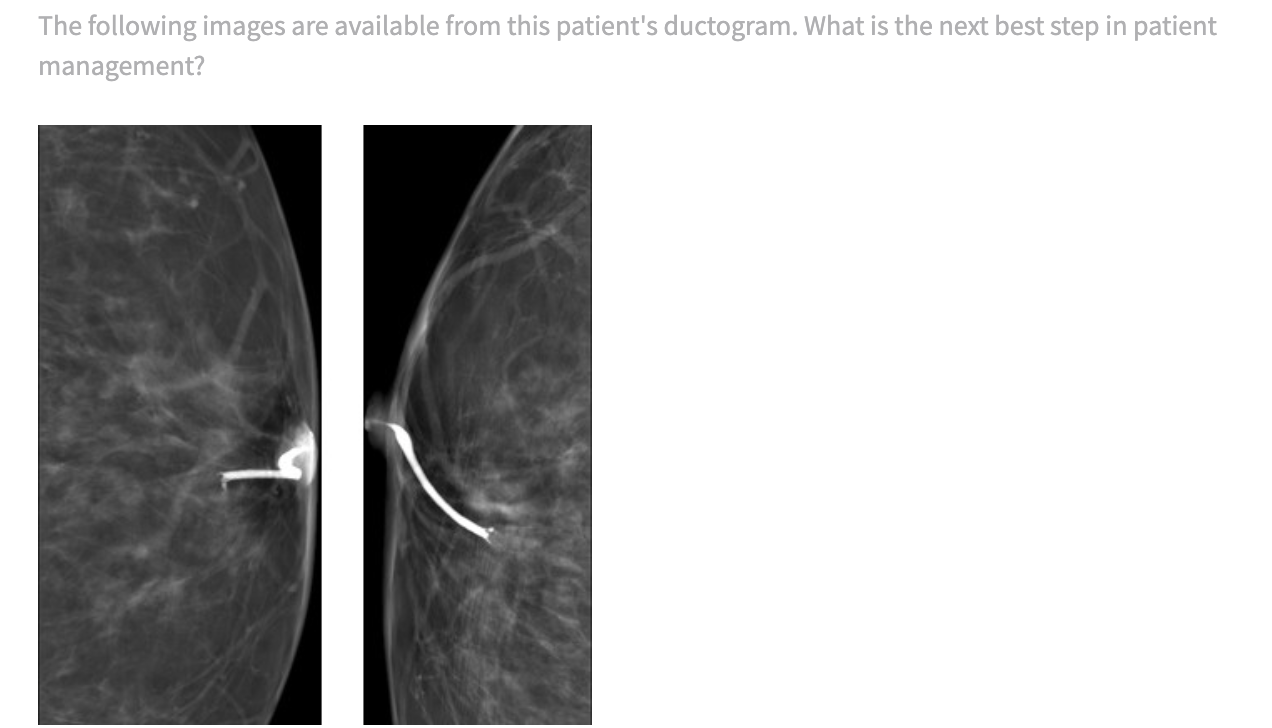

The patient should be referred back to a breast surgeon. In these images, an intraductal filling defect/mass is identified at the 6:00 position retroareolar. Primary differential diagnosis is papilloma or DCIS. Localizing this mass for a surgical breast biopsy will increase the probability of removing the etiology of the discharge rather than a blind surgical duct excision. The intraductal mass can be localized for subsequent surgical biopsy, either with a biopsy marker at the time of diagnostic ductogram or with a repeat ductogram/wire localization on the day of surgical biopsy. (from Core Review Breast)

Stereotactic breast biopsy is not indicated in this instance. The standard mammogram is most likely negative, which will make the intraductal mass difficult to localize for stereotactic biopsy. Also, a percutaneous biopsy may not remove the entirety of the mass.